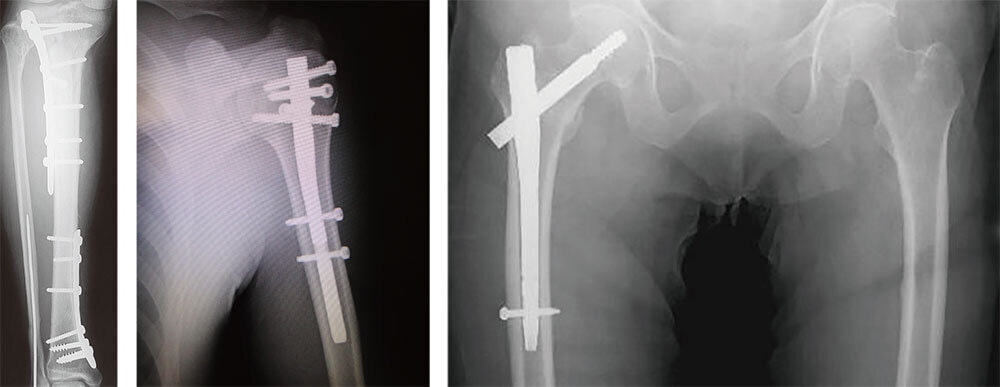

下腿骨骨折術後(左)

上腕骨頚部骨折術後(中央)

大腿骨転子部骨折術後(右)